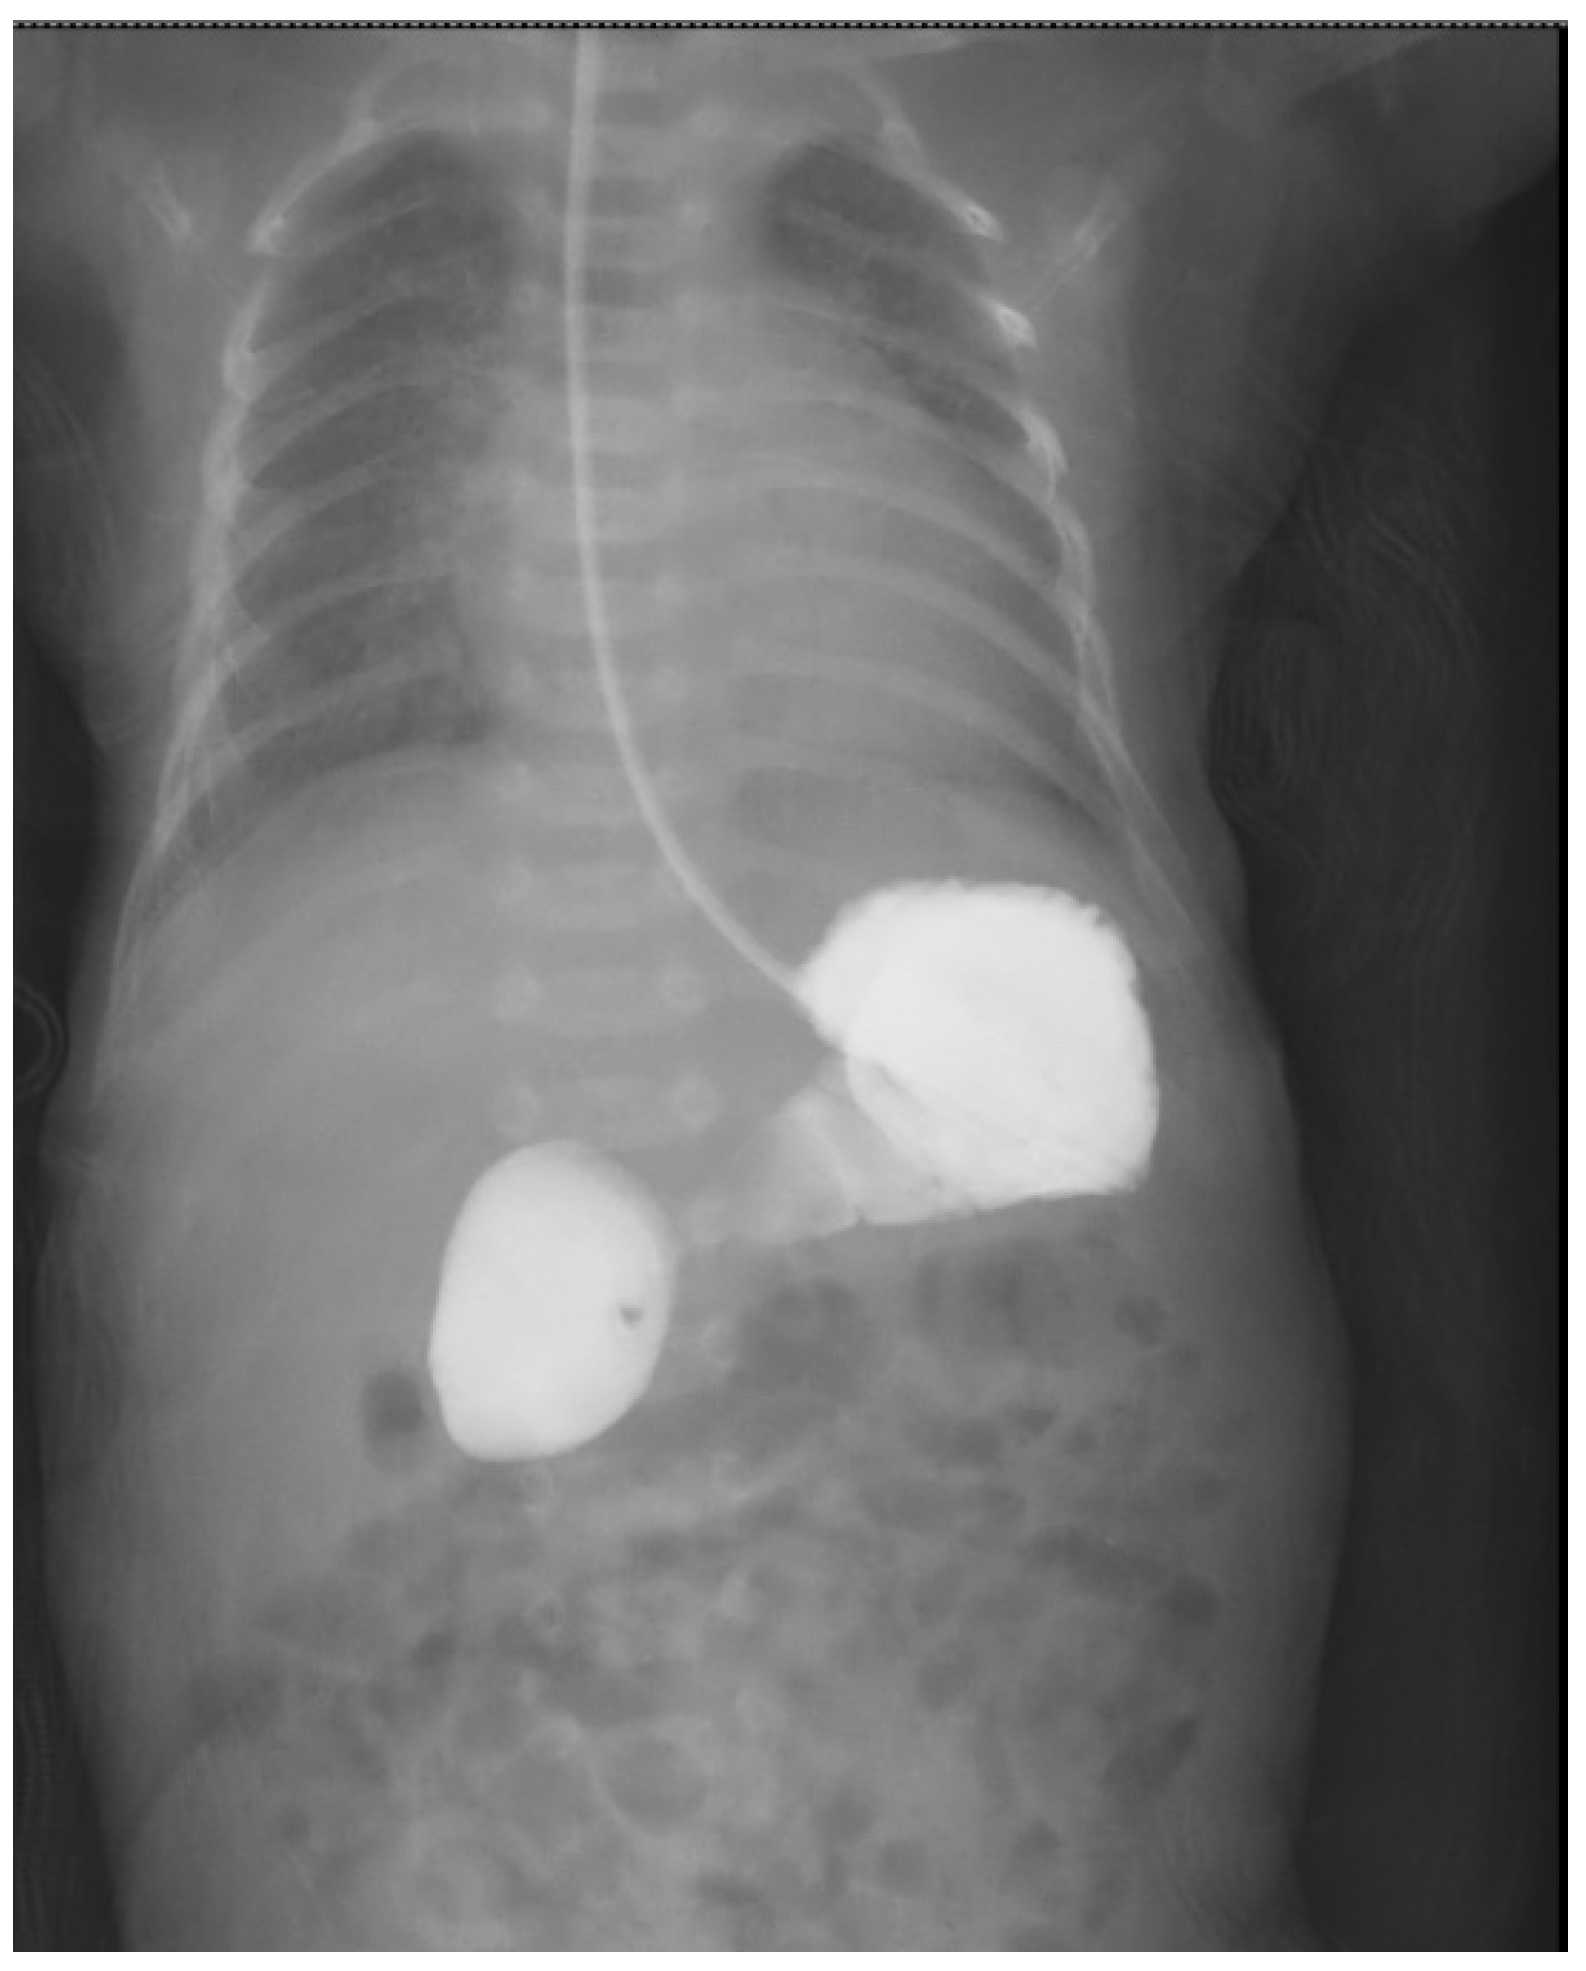

- Koberlein, G.; DiSantis, D. The “double bubble” sign. Abdom. Imaging 2016, 41, 334–335. [Google Scholar] [CrossRef] [PubMed]

- Traubici, J. The Double Bubble Sign. Radiology 2001, 220, 463–464. [Google Scholar] [CrossRef] [PubMed]